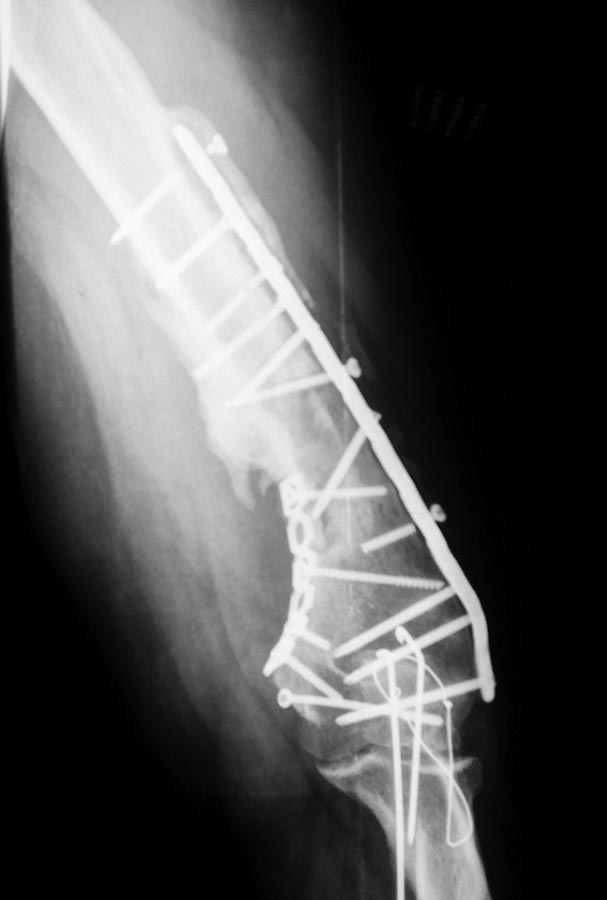

Уважаемые коллеги, хотелось бы услышать вашего мнения по поводу

непростого случая несросшегося перелома плечевой кости.

Пациент 44года в 2013г закрытый многооскольчатый перелом дистального

отдела правой плечевой кости. Остеосинтез пластинами в одной из

цифры).В августе 2015г удаление металлофиксаторов, невролиз лучевого

нерва, реостеосинтез (той же) пластиной, но в положеном

задне-латеральном положении.

При операции удалено около 50 куб. металлоза, при ревизии в месте

несращения были подозрительные творожистые включения, но кость выглядела

здоровой,все многократно промывал антисептиками, иссечены рубцы, края

отломков адаптированы друг к другу по типу замка - зона контакта

большая, суммарно кость укорочена около 1,5 см.

Неделю назад пациент стал говорить что появился хрукт. Рентген контроль

- перелом 2х винтов нестабильность вторичное смещение.

Предварительно планирую брать на ревизию удалить винты с проксимального

отдела, репозиция остеосинтез и дополнительно медиальная

реконструктивная? пластина.